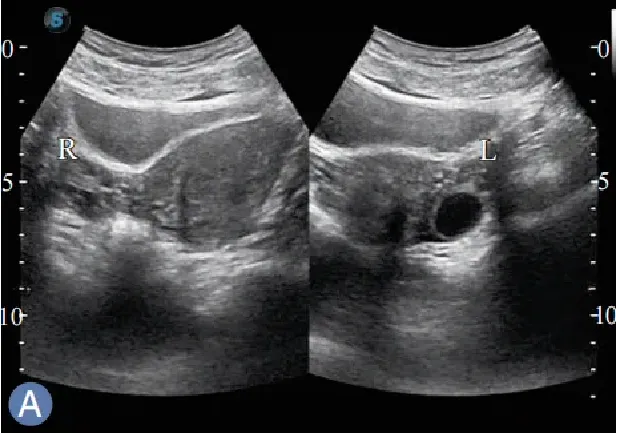

卵巢斜切扫查

仰卧位,扫查右( 左)侧卵巢探头斜置于耻骨联合左(右) 上方,对腹壁适当加压,使声束朝向右( 左)后方,以膀胱做透声窗,显示右(左)侧卵巢。